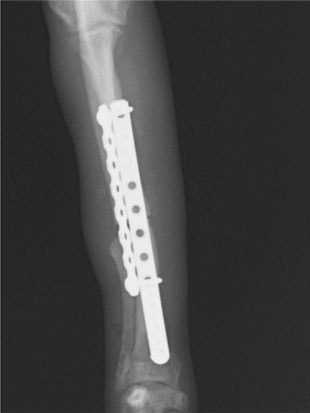

トイプードル 右遠位橈尺骨短斜骨折のALPSによる内固定

当院ではAdvanced Locking plate system(ALPS)と、Locking compression plate system(LCPS)という骨接合法で骨折症例の治療を行っています。

LCPは、スクリュー(ネジ)とプレート(金属の板)をロックする特殊な構造により骨折部位を固定する新しい世代のプレートシステムです。ひとつのホールでロッキングスクリューとスタンダードスクリューの使用を選択できるユニークな構造をしているため、骨折断端間の圧迫を目的とした従来型プレート固定法に加え、高い角度安定性を有するロッキングスクリューを用いた固定法の選択が可能です。従来のプレートシステムでは困難だった部分の骨折や癒合不全の症例に高い治療効果をもたらします。

従来型のプレートのように広い面積で骨と接するプレートを用いて固定を行った場合、プレート下の骨はプレートとの接触面において血行が絶たれ壊死し、それがリモデリングされると骨密度が低下する。この骨密度の低下防ぐために、骨折部局所への血行を温存することの重要性が近年改めて認識されるようになってきている。Advaed Locking Plate System (ALPS)は従来型のプレートシステムの欠点を改良し、より使いやすく、より骨への血行を阻害しないようにというコンセプトで作られた。